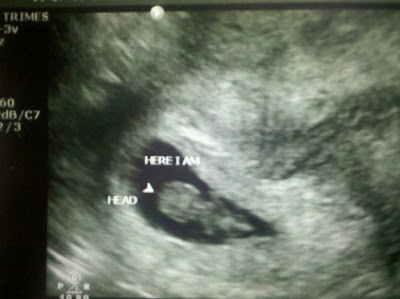

![]() |

| Here's our little peanut! 8.2 weeks along |